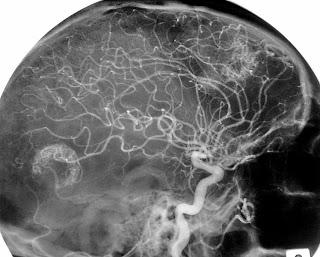

Métastases cérébrales (cliché datant de 1978)

Source: https://commons.wikimedia.org/wiki/File:M%C3%A9tastase_c%C3%A9r%C3%A9brales.JPG